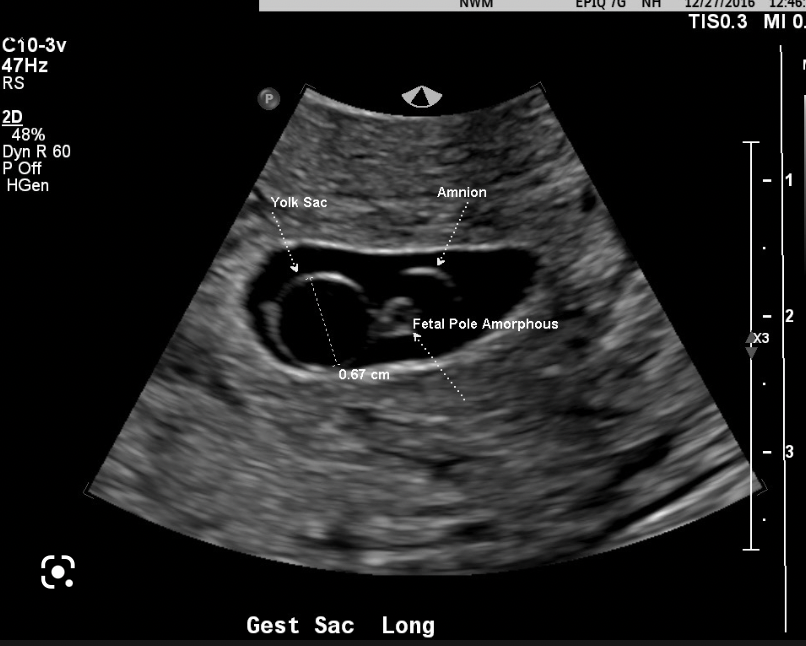

What 3 features are looked for on transvaginal US to determine the viability of a pregnancy?

A

• mean gestational sac diameter

• foetal pole + crown-rump length

• fetal heartbeat

mean gestational sac diameter

these appear sequentially so as each feature develops, the previous becomes less relevant in determining viability of a pregnancy

How is an anembryonic pregnancy diagnosed on transvaginal USS?

• a fetal pole is expected once mean gestational sac diameter is 25mm or more

• if the MGSD is >25mm and there is no fetal pole, scan is repeated after 1 week

• if the fetal pole is still not present, this is an anembryonic pregnancy